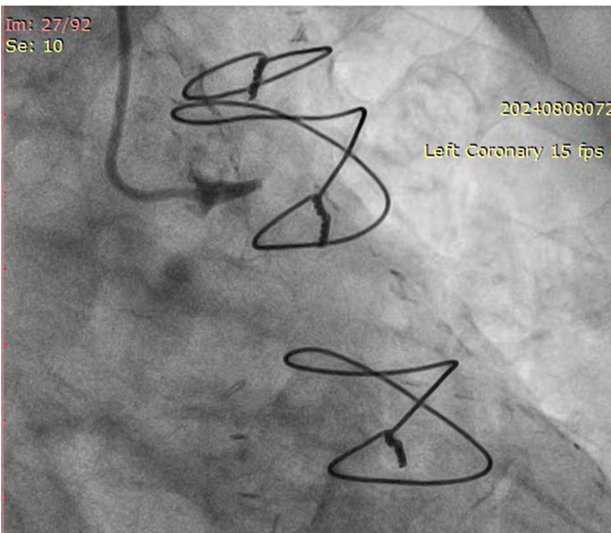

RSVG to Ramus to PLV was engaged with 7F AR-1 guide catheter. Occluded segment in RSVG crossed with Pilot-150 PTCA wire with Caravel micro-catheter and parked into distal RCA. Position of the wire and micro-catheter confirmed with retrograde injection from native LMCA. Retrograde wiring was attempted with Gaia NexT-2, Pilot-150, Pilot-200 PTCA guide wires, but was unsuccessful. Native RCA was engaged with 7F AL 0.75 guide catheter and antegrade wiring was attempted with micro-catheter support and Gaia NexT-2, Pilot-150 followed by Pilot-200 PTCA guide wires, but was unsuccessful. Balloon dilatation was done in proximal RCA with 2.0 x 10 mm SC balloon. Knuckle wire technique was used to cross the lesion from antegrade site but unsuccessful. Finally, lesion crossed with Asahi Gladius MG-14 wire from antegrade approach and wire parked into the RSVG. Micro-catheter exchanged. Serial predilatation was done with 0.75 x 8 mm SC balloon followed by 2.0 x 20 mm SC balloon. IVUS run was taken for vessel size estimation. 3.0 x 48mm DES was deployed from proximal RCA. Post dilatation was done with NC 3.5 x 8 mm balloon. Distal RCA was addressed with 2.75 x 30 mm DEB. Mid RCA was stented with DES 3.00 x 32 mm. Post-dilated with 3.0 x 10 mm NC balloon followed by 3.75 x 8 mm NC balloon. Post-stenting IVUS run showed good stent expansion and apposition. Distal TIMI-III flow was achieved.

Case Summary